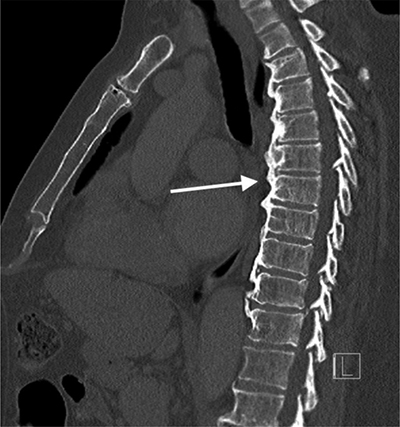

Figure 3

CT thorax sagittal images in bone window.